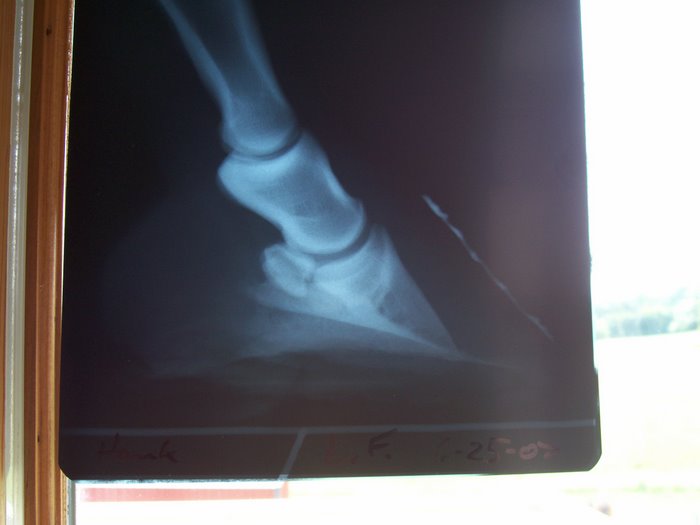

Here are his x-rays from 2007 a couple mos. after founder.

Here are x-rays from late April of this year

I don't know if that might help or not.

Thanks Angie, I believe she is right, he did take a lot of wall vertically, but it was all stretched out. He was sore before the trim, but not terribly.

He foundered twice. Once in 2005, and last year. He is VERY thin soled. Rotation was approx 8 degrees in both according to vet. And I believe she did see bruising, not the whole sole, but right at the tip by the toe the rest is betadine. UGHHH I imagine that is where the coffin bone is. I noticed it in one of the pics I didn't post, I think the betadine made it more obvious, I didn't see it before applying it. I will show you that pic.